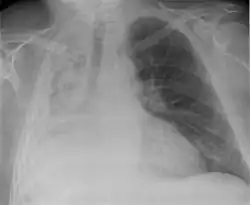

Hemothorax

Massive right sided pleural effusion later confirmed to be a hemothorax

Hemothorax, or accumulation of blood in the pleural space, can result from trauma or surgical procedures in the chest. This accumulation of blood can grow large enough to compress the lung and push away other structures in the chest, thus causing a mediastinal shift.[6] On a chest x-ray, a hemothorax can appear similarly to a pleural effusion with blunting of the pleural recess and white out of normal lung zones.[7] In the setting of traumatic chest injury, rib fractures are also commonly observed on x-ray.[8]